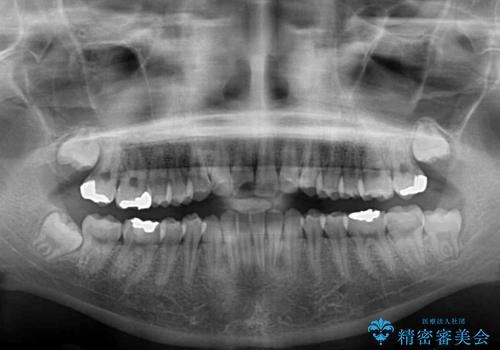

- 歯並びと虫歯をきれいにしたいとのことで来院された患者様です。

楽して短期間で歯列を整えたいとのことで、ワイヤー装置を用いて矯正治療を行い、矯正治療後に下顎の虫歯はセラミックインレー、上顎はPGAインレー(ゴールドインレー)、根管治療を行う歯についてはオールセラミッククラウンにて補綴治療を行うこととしました。

保険治療で用いる樹脂(コンポジットレジン)で行った虫歯治療は、周辺が変色して汚くなっていましたが、下顎はセラミックインレーで審美的に、上顎はPGAインレーで歯に負担の少ない治療を行うことができました。